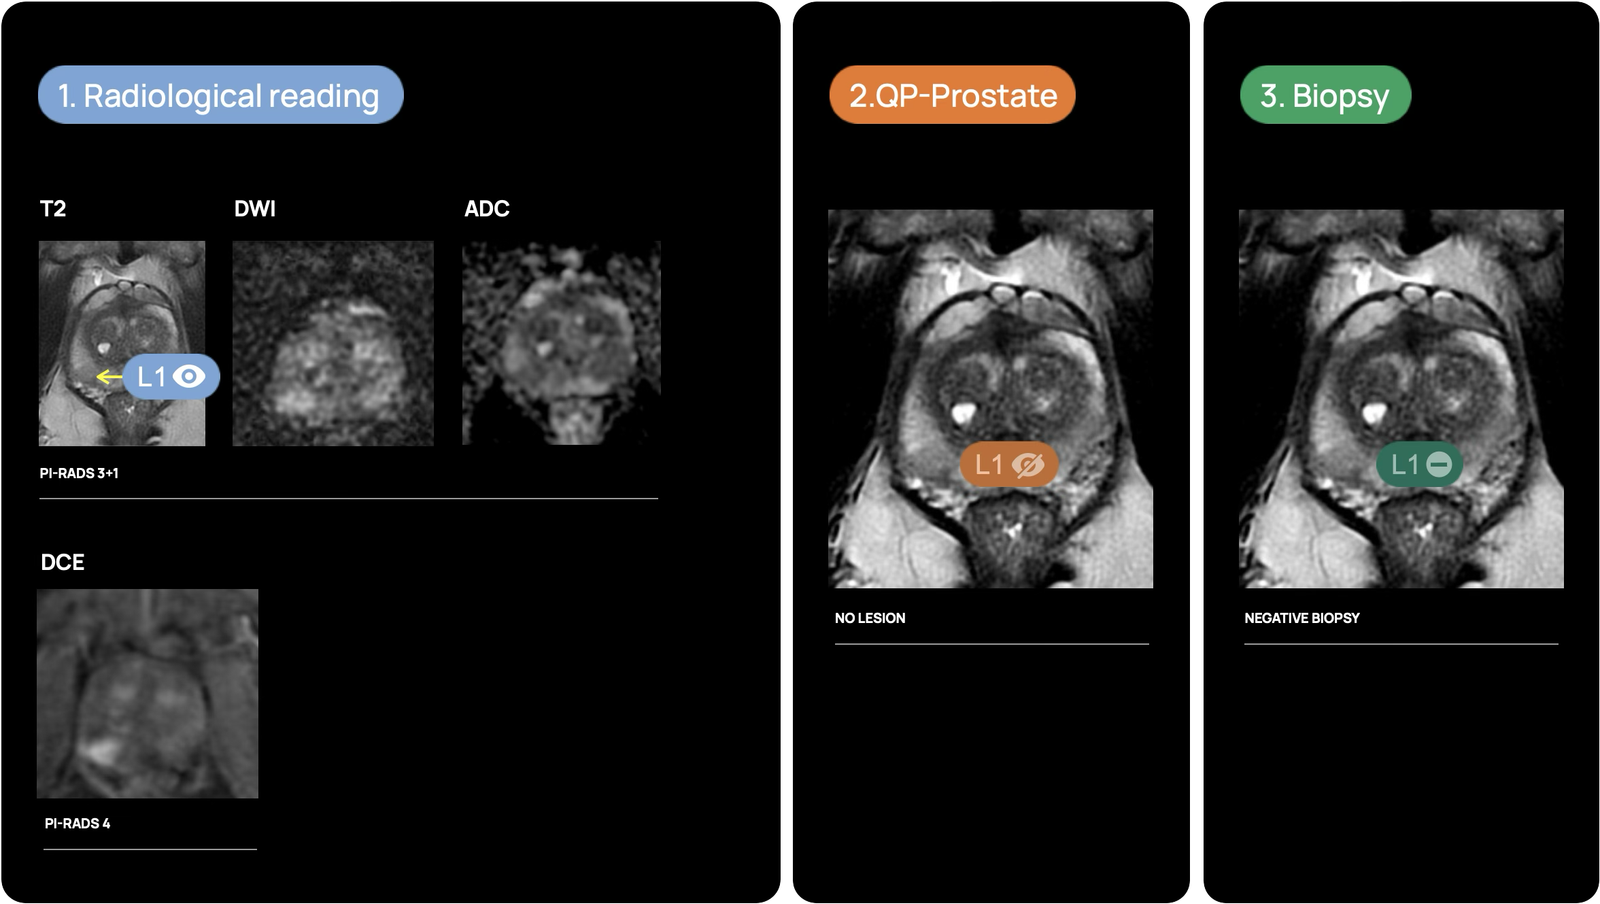

How does it work?

Changing the narrative in prostate diagnosis thanks to maximum accuracy in prostate MRI interpretation

In short, QP-Prostate leverages advanced artificial intelligence image processing techniques to offer a state-of-the-art approach to prostate MRI interpretation. This image processing software is compatible with standard workstations and allows for the visualization and analysis of DICOM data by qualified professionals.

QP-Prostate is setting a new standard for accuracy, speed, and diagnostic precision. Its AI algorithm identifies and stratifies by likelihood intermediate and high-grade aggressive prostate cancer lesions, and provides a segmentation of the prostate. This allows Health Care Professionals to improve their diagnostic accuracy and fusion biopsy planning.

QP-Prostate automatically identifies and highlights prostate regions suspicious for aggressive prostate cancer, assigning each a confidence-based classification score.